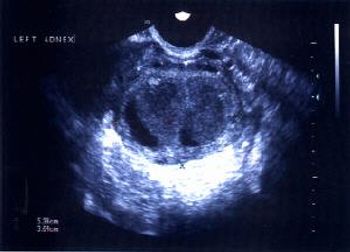

This is a confirmed case of scar ectopic pregnancy. Yesterday, I carried out this exam in an emergency room, without much time to perform an adequate sonogram, the patient did not feel good with “cramps” but no signs of bleeding.